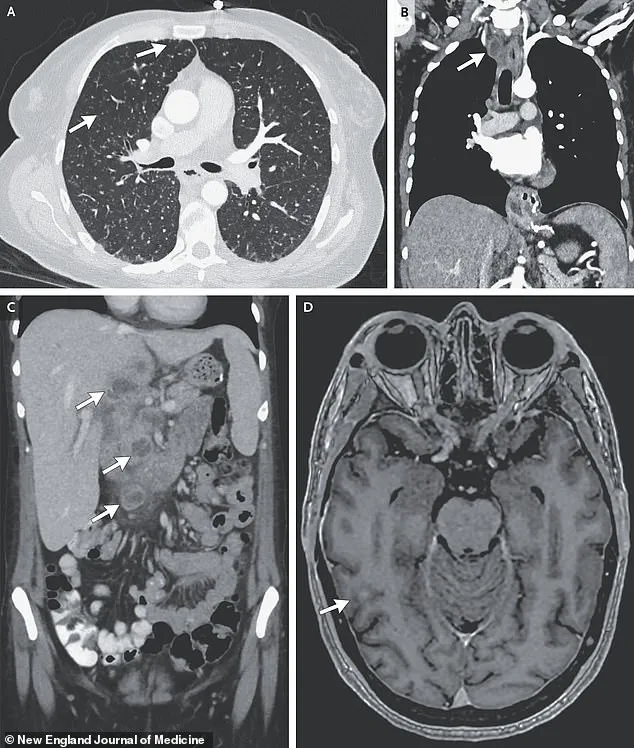

Further imaging uncovered lesions in her liver, lymph nodes, pancreas, and brain—findings that pointed to a systemic infection.

The woman’s TB had progressed to a rare and severe form known as disseminated tuberculosis, in which the infection spreads beyond the lungs to multiple organs, including the brain.

In rare but devastating instances, TB can affect the brain, leading to complications such as increased intracranial pressure, nerve cell death, and subsequent paralysis or strokes.

The woman in the report had nodules detected in multiple organs, including her lungs, lymph nodes, liver, pancreas, and brain, as revealed by medical imaging.